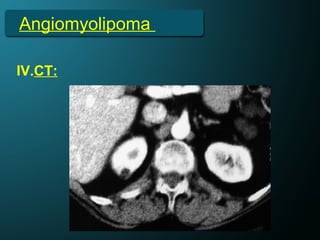

Angiomyolipoma

IV.CT: